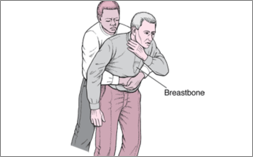

Emergencies And Injuries - Merck Manuals Consumer Version

www.merckmanuals.com

www.merckmanuals.com

choking emergencies